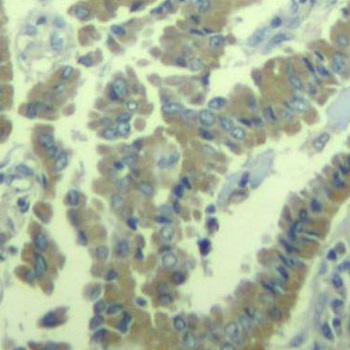

• AP0404: image 2

Immunohistochemical analysis of paraffin-embedded human lung carcinoma tissue using Phospho-MARCKS-S170 antibody.